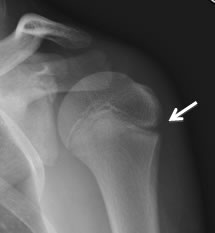

Little League shoulder also called proximal humeral epiphyseolysis is an inflammation of the growth plate on the upper humerus in young athletes. It is important for treatment to ensure the bone growth plate is not damaged and is allowed to heal properly. By strengthening the muscles around the shoulder and learning proper throwing mechanics and stretching techniques the patient can build up his or her arm.

Physical therapy is usually recommended to strengthen the muscles in the upper arm and shoulder during recovery. Treatment is cessation of throwing followed by PT and progressive throwing program after sufficient rest. Premature closure and fractures of the growth plate have been reported in association with Little League shoulder but these are extremely rare complications.